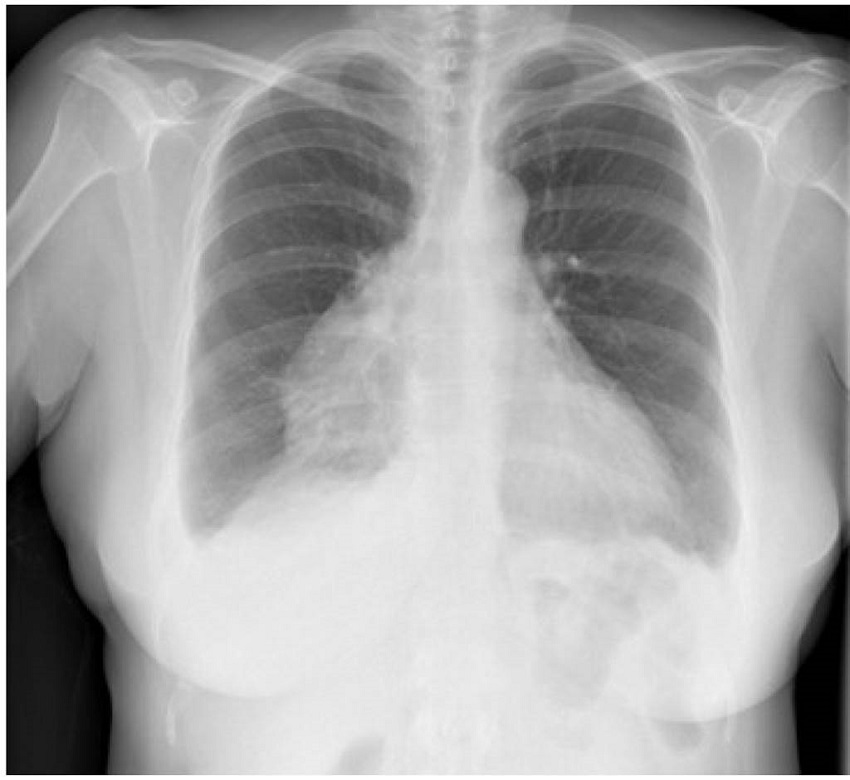

En urgencias hospitalarias, el estudio se completó con una prueba de laboratorio, en la que se objetivó un aumento de los reactantes de fase aguda (proteína C reactiva 118,7 mg/L y fibrinógeno 692 mg/ dL), sin aparición de otros hallazgos sugestivos de infección ni elevación de marcadores de daño miocárdico o indicadores de insuficiencia cardíaca. También se le hizo una radiografía de tórax, en la que se apreció una imagen compatible con cardiomegalia versus masa mediastínica anterior, con una pérdida de volumen en lóbulo inferior derecho y derrame pleural bilateral (figuras 1 y 2).